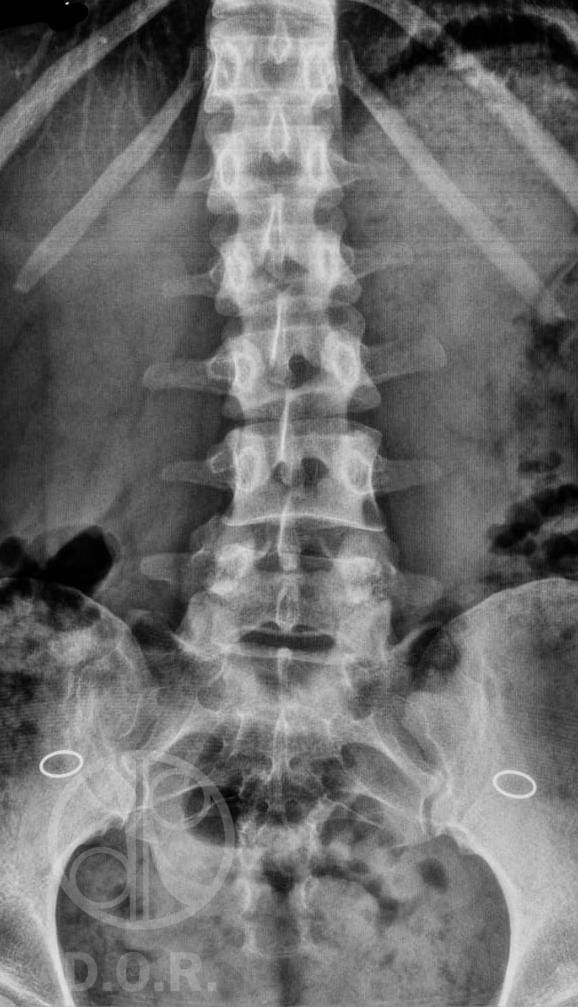

• Radiografías de Columna: Visualización de la columna vertebral para detectar desviaciones, fracturas o enfermedades degenerativas.

• Radiografías de Abdomen: Evaluación de órganos abdominales y estructuras óseas para identificar obstrucciones o cálculos.